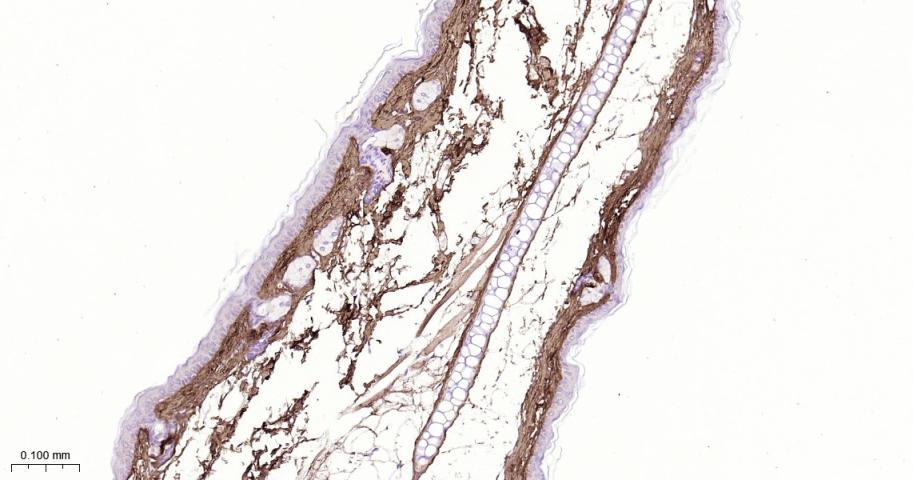

Paraformaldehyde-fixed, paraffin embedded Rat Skin; Antigen retrieval by boiling in sodium citrate buffer (pH6.0) for 15 min; The section was incubated with Collagen I Polyclonal Antibody, Unconjugated (bs-10423R) at 1:800 overnight at 4°C, followed by conjugation to the bs-0295G-HRP and DAB (C-0010) staining.

Paraformaldehyde-fixed, paraffin embedded Mouse Skin; Antigen retrieval by boiling in sodium citrate buffer (pH6.0) for 15 min; The section was incubated with Collagen I Polyclonal Antibody, Unconjugated (bs-10423R) at 1:800 overnight at 4°C, followed by conjugation to the bs-0295G-HRP and DAB (C-0010) staining.